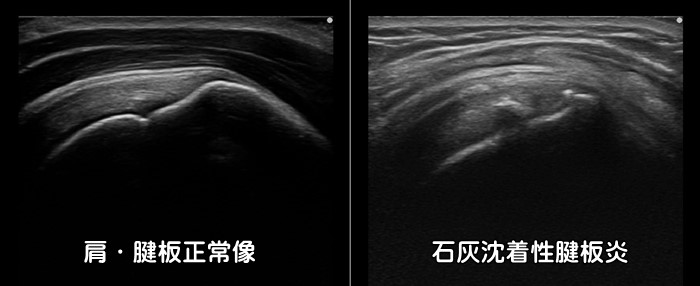

石灰沈着性腱板炎

肩を真横へ上げていく外転動作での痛みが強いのが特徴です。急性型の場合は前日まで全く症状がなく、朝起きると激痛で肩が上がらなくなります。10日前後で痛みは消失しますが慢性型の場合は数年にわたって肩の痛みが続き、年のせいだと石灰沈着に気が付かない場合もあります。好発部位は肩の棘上筋・棘下筋と呼ばれる筋肉内ですが、石灰は体の至る所に沈着します。